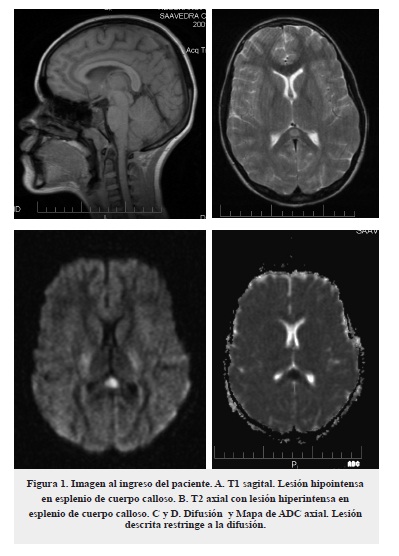

El síndrome de lesión esplénica reversible (RESLES) corresponde a una lesión transitoria presente en un espectro de entidades con características clínicas y radiológicas definidas con buen pronóstico. La lesión esplénica reversible con encefalopatía/encefalitis leve (MERS) hace parte de este grupo de enfermedades. Presentamos el caso de una niña con un cuadro clínico que inicia con un pródromo febril y evoluciona hacia alteración de estado de conciencia. Se realiza resonancia magnética (RMN) cerebral simple que muestra lesión en el esplenio del cuerpo calloso hipointensa en T1 e hiperintensa en T2 y FLAIR, con restricción en la difusión y mapa de ADC. La sintomatología y los hallazgos radiológicos se resolvieron a partir de las 4 semanas. El cuadro clínico y el curso imagenológico de este caso corresponde a un cuadro típico de MERS. Esta entidad tiene baja incidencia y es poco conocida en nuestro país, razones por las cuales el diagnóstico es difícil en la mayoría de los casos.

The Reversible Splenial Lesions Syndrome (RESLES) has been described as a transient lesion in a group of diseases with special clinical and radiological features and with a good prognosis. An encephalopathy with a reversible splenium of the corpus callosum lesion (MERS) is part of these diseases. We present a case report of an 11 years old female with a febrile prodromal phase that evolved into an altered state of consciousness. Simple brain MRI findings comprise a lesion in the splenium of the corpus callosum, hypointense on T1, hyperintense on T2 and FLAIR, with restricted diffusion on ADC. The clinical symptoms and radiological findings resolved after 4 weeks. The clinical course and images of this case are typical presentation of MERS. This entity has a low incidence and not very renowned in our country, for this reason, the diagnosis is difficult in most cases.

Paciente femenina de 11 años, quien consultó al servicio de urgencias por un cuadro de 3 días de evolución, inició con cefalea pulsátil frontal que empeoró progresivamente y posteriormente se acompañó de disartria, dificultad en la marcha con aumento del polígono de sustentación, fiebre cuantificada y somnolencia. No presentaba antecedentes médicos de importancia. Al examen físico de ingreso a urgencias se encontró un puntaje en la escala Glasgow de 10/15 (ocular 3, verbal 2, motor 5) con pobre seguimiento de instrucciones, escasa movilización espontánea de miembros superiores, todos los reflejos normales y sin signos meníngeos. Se consideró inicialmente como primera posibilidad diagnostica encefalitis y se iniciaron estudios, incluyendo una RMN cerebral simple y con contraste que mostró una lesión única en esplenio de cuerpo calloso hipointensa en T1 e hiperintensa en T2 y FLAIR, que restringe a la difusión en mapa de ADC, sin realce con el medio de contraste (figura 1). Se tomó estudio de líquido cefalorraquídeo (LCR) que mostró pleocitosis (184 células x mm3) linfocitaria (60 %), hiperproteinorraquia (125 mg/dL), lactato ligeramente elevado (3 mmol/L), con el resto de parámetros dentro de los rangos normales. El cultivo bacteriano y la reacción en cadena de la polimerasa (PCR) para Herpes I y II fueron negativos. Se completaron estudios con búsqueda de causas autoinmunes para lo cual se solicitaron: anticitoplasma de neutrófilo, complemento (C3 y C4), complemento CH50, anticardiolipinas IGG e IGM, anticuerpos anti ADN de doble cadena, Anti Ro y Anti Smith que estuvieron dentro de rangos normales. Se amplió estudio imagenológico con RMN de columna simple y contrastada, la cual no presentó lesiones.

En estudios imagenológicos de esta entidad se aprecian lesiones hipointensas en T1, hiperintensas en T2 y que restringen en difusión en mapa de ADC, las cuales involucran en todos los casos el esplenio del cuerpo calloso. Se ha subclasificado la entidad en MERS tipo1 y tipo 2 según la extensión de la lesión, en el primer caso la lesión está circunscrita al esplenio del cuerpo calloso, mientras que, en el segundo puede extenderse a lo largo de todo el cuerpo calloso y a la sustancia blanca extracallosal, principalmente frontoparietal. De estos dos patrones el primero es de mejor pronóstico1,2.